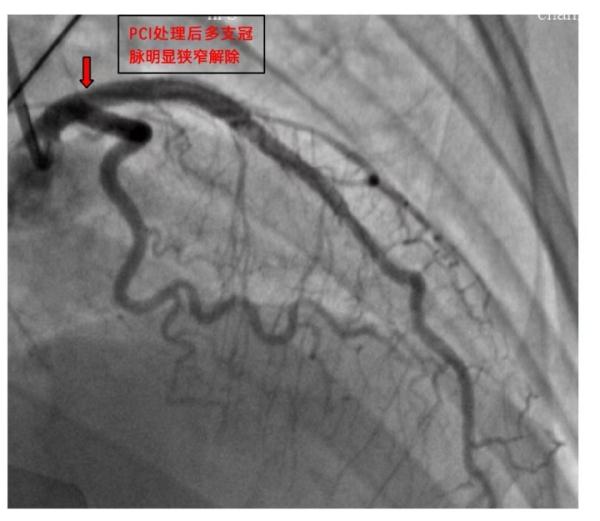

心血管内科五病区主任容志毅及其介入手术团队,迅速拟定最优方案,精准“打击”病变血管,在历时三个小时后,成功为患者植入支架,开通血管,化险为夷。术后,患者被送入CCU进行后续治疗。目前,患者病情好转,已出院回家休养。

△术后